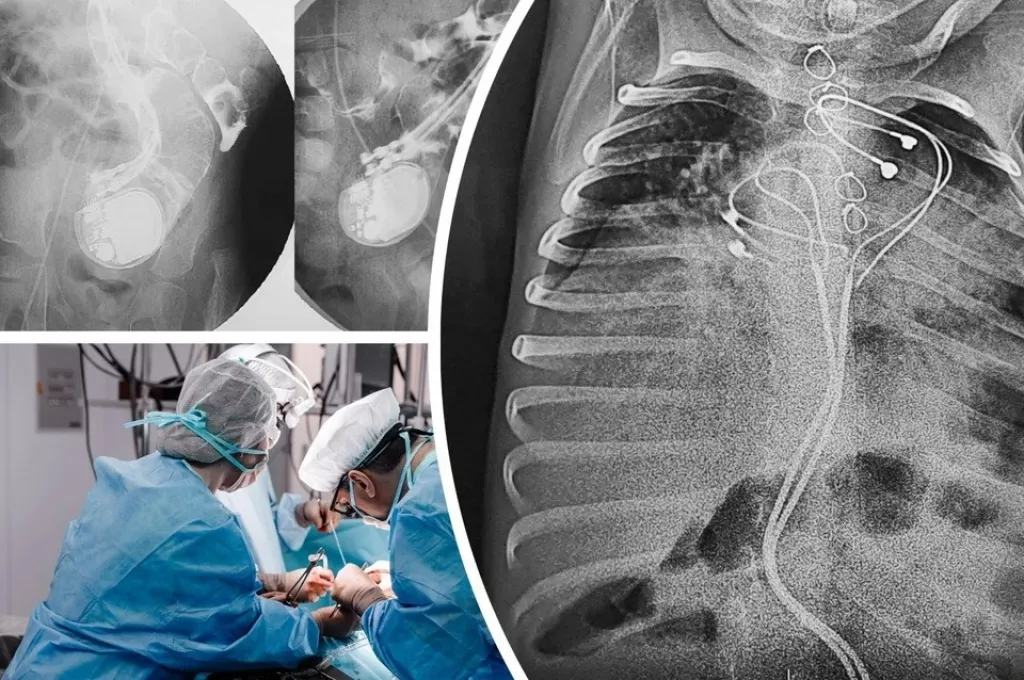

Хирурги клиники Мешалкина и Новосибирской областной больницы спасли 3-летнего ребенка с кардиостимулятором в кишечнике. Ребенок родился с редкой жизнеугрожающей аритмией, которая встречается у 1 из 25 тысяч новорожденных. Ему установили кардиостимулятор, который буквально всосался в живот, сообщает «КП-Новосибирск».

— Из-за малого размера тела малыша кардиостимулятор не получилось установить в грудную клетку, как взрослым пациентам. Поэтому его разместили в верхней части живота, поверх брюшины и прямой мышцы. Электроды прикрепили к правому предсердию и верхушке правого желудочка, — объяснили в НМИЦ им. ак. Е.Н. Мешалкина.

Через три года мальчика привезли в больницу Барнаула с высокой температурой и симптомами кишечной непроходимости. Кардиостимулятор в месте имплантации не прощупывался, а на рентгене выяснилось, что устройство проникло в кишечник. Там оно продолжало исправно работать и задавать ритм сердцу.

— Кардиохирурги Тимур Хапаев и Сергей Иванцов имплантировали однокамерный кардиостимулятор в грудь, а хирурги Владислав Цыганок и Юрий Койнов извлекли устройство, отсекли инфицированные электроды и закрыли дефект кишечной стенки. После курса антибактериальной терапии на десятый день ребенок был выписан в удовлетворительном состоянии, — рассказали в новосибирской клинике.